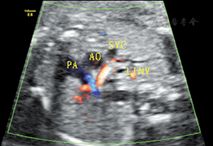

孕妇31岁,孕27+1周,产前常规行胎儿超声心动图检查。既往体健,无传染病及遗传病史,孕期顺利。超声显示:胎儿心脏位于胸腔内,位置正常,心尖指向左前方。心轴及心胸比值正常。各心腔内径比值正常,室壁厚度及运动正常。各瓣膜形态及启闭未见明显异常,彩色多普勒血流显像未见异常血流信号。三血管–气管切面:肺动脉左侧可见管状回声,内径0.21 cm(图1),探头于该切面向胎儿头侧偏转,可见其跨越右肺动脉上方,于主动脉弓下方从左向右径直走行,在距上腔静脉右心房入口约0.61 cm处汇入其中,其内可见静脉频谱(图2)。主动脉弓长轴切面:主动脉弓下方可见两个管状回声,呈"双眼征",其中前下方为右肺动脉横断面,后上方为异常血管断面;彩色多普勒示二者血流方向相反(图3)。余切面未见明显异常。心律规整,心率148次/min。超声提示:胎儿左无名静脉走行异常(主动脉弓下走行)。产后经超声及心血管造影证实。

在胚胎发育的第7周,左、右两侧的前主静脉借血管丛连接成一条斜行的血管,即无名静脉。随着左无名静脉发育形成后,左侧前主静脉和Cuvier管逐渐闭塞,左上腔静脉退化,右侧前主静脉与Cuvier管发育成为正常的右上腔静脉[1]。左、右无名静脉分别接收左、右颈总静脉和左、右锁骨下静脉的静脉血,汇总成上腔静脉,自右房上面注入右房。正常情况下,左无名静脉由左向右斜行跨过主动脉弓上方,汇入上腔静脉。但本例中,三血管–气管切面向胎儿头侧偏转动态扫查显示左无名静脉在主动脉弓下方与右肺动脉上方之间横过主动脉弓,在上腔静脉入右心房处同上腔静脉汇合;主动脉弓长轴切面也可显示主动脉弓与右肺动脉间存在一圆形静脉血管结构,而正常情况下,主动脉弓下仅有右肺动脉的横断面;三血管–气管切面肺动脉左侧可见一管状回声,为静脉频谱,这是由低位走行即主动脉弓下走行的左无名静脉所致。关于三血管–气管切面肺动脉左侧发现异常管状回声,有以下三种可能:①永存左上腔静脉Ⅰ型,左上腔静脉血经冠状静脉窦入右房,此型约占90%以上。超声表现:四腔心观左房室沟交界处见扩张的冠状静脉窦;三血管切面肺动脉左侧出现一静脉血管,呈"四血管"改变,且该静脉频谱与右上腔静脉频谱或肺静脉频谱相似;旋转探头,发现该静脉与冠状静脉窦相连且血流方向与右上腔静脉相同。②完全性肺静脉异位引流心上型,四腔心观看不到正常回流入左心房的4支肺静脉,左心房后方可见异常血管,为垂直静脉;三血管–气管切面肺动脉外侧可见管状回声,但血流方向与右上腔静脉相反,为上行的垂直静脉,先后汇入左无名静脉及右上腔静脉。③伪像,由于切面偏斜,将左房的一部分也包括在其内,若此时观察到4支肺静脉均回流入左心房,即为伪像所致。排除以上几种情况,特别是排除了严重危及新生儿存活的完全性肺静脉异位引流,本研究即可考虑左无名静脉主动脉弓下走行的可能。综上所述,超声表现为三血管–气管切面肺动脉左侧异常管状回声,主动脉弓长轴下方出现"双眼征",且二者血流方向不同,并且无其他心内外结构异常时可以诊断为左无名静脉主动脉弓下走行。